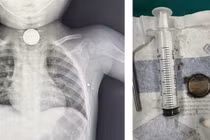

Vừa qua, Bệnh viện Sản Nhi tỉnh Quảng Ninh tiếp nhận bệnh nhi L.M.K 21 tháng tuổi, (thị xã Quảng Yên), nhập viện trong tình trạng tỉnh, ho sặc sụa, ho có đờm, thở khò khè.

Khoa Nội Tiêu hóa Bệnh viện Nhi Đồng Cần Thơ vừa điều trị thành công trường hợp bệnh nhi nuốt dị vật tiêu hóa bằng kĩ thuật nội soi thực quản dạ dày tá tràng, gắp dị vật bằng ống mềm.